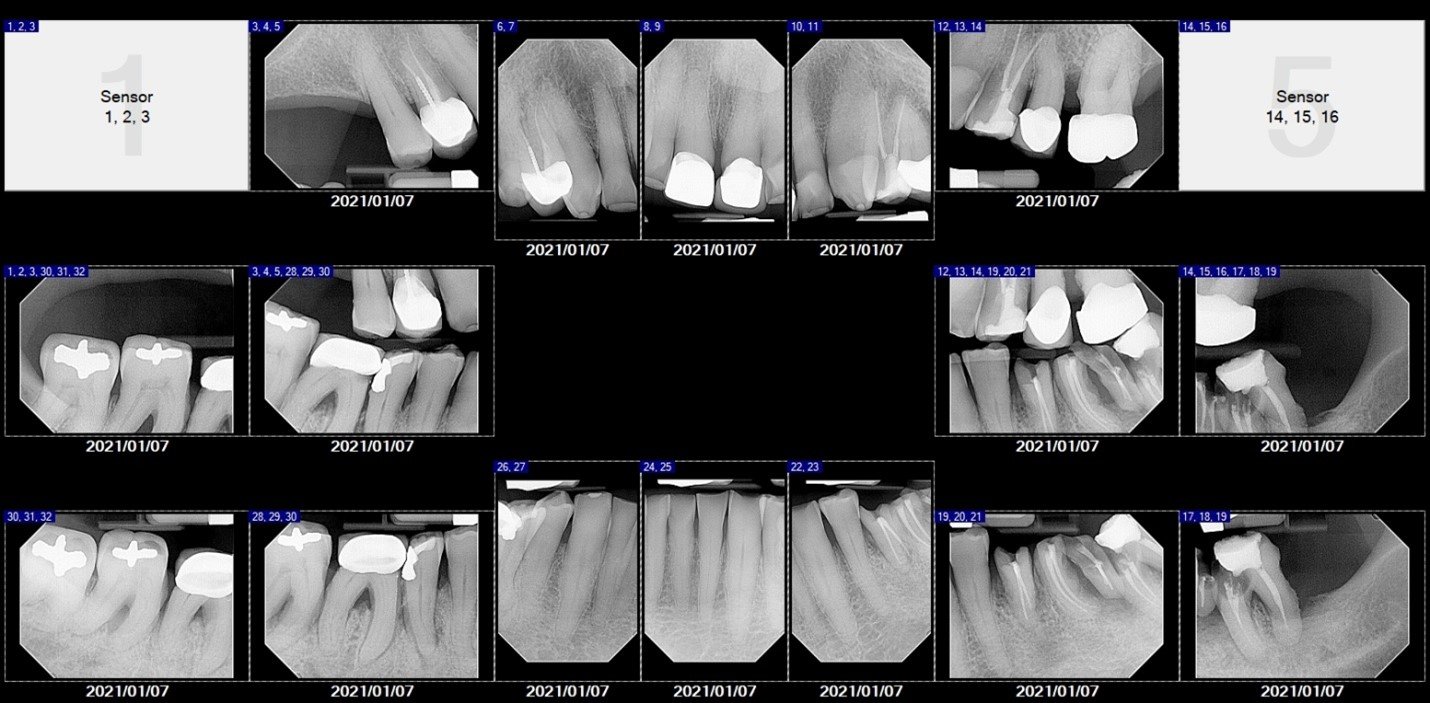

After a thorough dental and medical evaluation, including a complete set of x-rays and CBCT, a plan was developed for him. This included the removal of all broken and infected teeth, rebuilding the lower anterior teeth to improve his anterior occlusion, restoring the teeth that could be saved, and placing implants in the future edentulous sites of the lower arch. You can see on the x-rays and CBCT these areas.